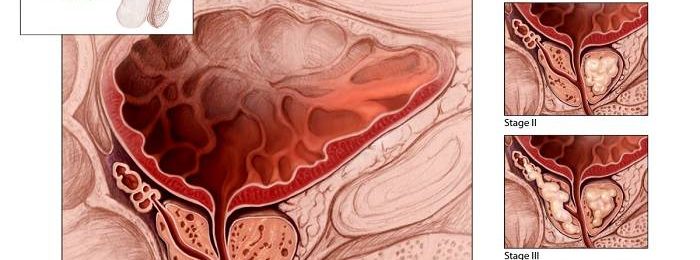

Выделяется три стадии аденомы простаты: компенсированная, субкомпенсированная и декомпенсированная. На компенсированной стадии меняется динамика акта мочеиспускания. Оно становится более частым, менее интенсивным и менее свободным. Появляется необходимость 1-2 раза помочиться ночью. Как правило, никтурия на I стадии аденомы простаты не вызывает беспокойства у больного, который связывает постоянные ночные пробуждения с развитием возрастной инсомнии.

Днем нормальная частота мочеиспускания может быть сохранена, однако пациенты с I стадией аденомы простаты отмечают период ожидания, особенно выраженный после ночного сна. Затем частота дневных мочеиспусканий увеличивается, а объем мочи, выделяемой за однократное мочеиспускание, уменьшается. Возникают императивные позывы. Струя мочи, которая ранее образовывала параболическую кривую, выделяется вяло и падает практически вертикально. Развивается гипертрофия мышц мочевого пузыря, благодаря которой сохраняется эффективность его опорожнения. Остаточной мочи в мочевом пузыре на этой стадии нет или практически нет (менее 50 мл). Функциональное состояние почек и верхних мочевыводящих путей сохранено.

На II стадии аденомы предстательной железы мочевой пузырь увеличивается в объеме, в его стенках развиваются дистрофические изменения. Количество остаточной мочи свыше 50 мл и продолжает увеличиваться. На всем протяжении акта мочеиспускания больной вынужден интенсивно напрягать мышцы брюшного пресса и диафрагмы, что приводит к еще большему повышению внутрипузырного давления. Акт мочеиспускания становится многофазным, прерывистым, волнообразным. Постепенно нарушается пассаж мочи по верхним мочевыводящим путям. Мышечные структуры теряют эластичность, мочевые пути расширяются. Нарушается функция почек. Пациентов беспокоит жажда, полиурия и другие симптомы прогрессирующей хронической почечной недостаточности. При срыве механизмов компенсации наступает третья стадия.

Мочевой пузырь у больных с III стадией аденомы простаты растянут, переполнен мочой, легко определяется пальпаторно и визуально. Верхний край мочевого пузыря может доходить до уровня пупка и выше. Опорожнение невозможно даже при интенсивном напряжении мышц брюшного пресса. Желание опорожнить мочевой пузырь становится непрерывным. Возможны сильные боли внизу живота. Моча выделяется часто, каплями или очень малыми порциями. В дальнейшем боли и позывы к мочеиспусканию постепенно ослабевают. Развивается характерная парадоксальная задержка мочи, или парадоксальная ишурия (мочевой пузырь переполнен, моча постоянно выделяется по каплям).

Верхние мочевыводящие пути расширены, функции почечной паренхимы нарушены вследствие постоянной обструкции мочевых путей, приводящей к повышению давления в чашечно-лоханочной системе. Нарастает клиника хронической почечной недостаточности. Если медицинская помощь не оказывается, больные погибают от прогрессирующей ХПН.